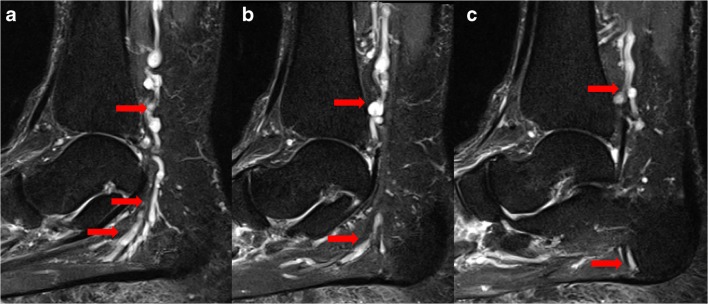

Plantar heel pain is a common presenting complaint to orthopedic surgery practices. While differential diagnoses for neuropathic pain include plantar fasciitis, fat pad inflammation, stress fractures, and inflammatory arthropathy, the entrapment of the first branch of the lateral plantar nerve (inferior calcaneal nerve, also known as Baxter’s nerve) is often missed as an additional cause of pain in this region (Fig. 12) [72]. Also referred to as distal tarsal tunnel syndrome or Baxter’s neuropathy, this condition often presents in runners, ballet dancers, and gymnasts and must be considered in athletes [26]. In these patients, the first branch of the lateral plantar nerve is compressed between the fascia of the abductor hallucis muscle and the medial side of the quadratus plantae muscle within the tarsal tunnel as it travels to innervate the abductor digiti quinti muscle [20, 24]. The isolated nerve entrapment presents as neuropathic pain after prolonged activity, likely due to ischemia of the nerve from engorgement of the accompanying branches of the lateral plantar artery [51]. Patients present with maximal tenderness at the location of nerve entrapment, along the medial border of the plantar heel [51].

Fig. 12.

Sagittal short-tau inversion recovery images (a, b, c) demonstrate varicosities (arrows) in the tarsal tunnel compressing Baxter’s nerve (inferior calcaneal nerve—the first branch of the lateral plantar nerve), resulting in fatty replacement of the abductor digiti quinti.

MRI is useful in identifying lateral plantar nerve entrapment through detection of muscle alterations associated with denervation [72]. In acute and subacute muscle denervation, fluid-sensitive MRI sequences, specifically proton-density and T2-weighted sequences, demonstrate hyperintense signal within the abductor digiti quinti muscle, corresponding to neurogenic muscle edema (Fig. 13a, b) [72]. Chronic denervation leads to atrophy and irreversible fat infiltration that are well depicted on T1-weighted images, demonstrating significant volumetric reduction of the abductor digiti quinti muscle with occupied fatty tissue. Through clear depiction of osseous and soft tissue structures in the heel region, MRI provides highly accurate diagnostic methods to evaluate for lateral plantar nerve entrapment [24].